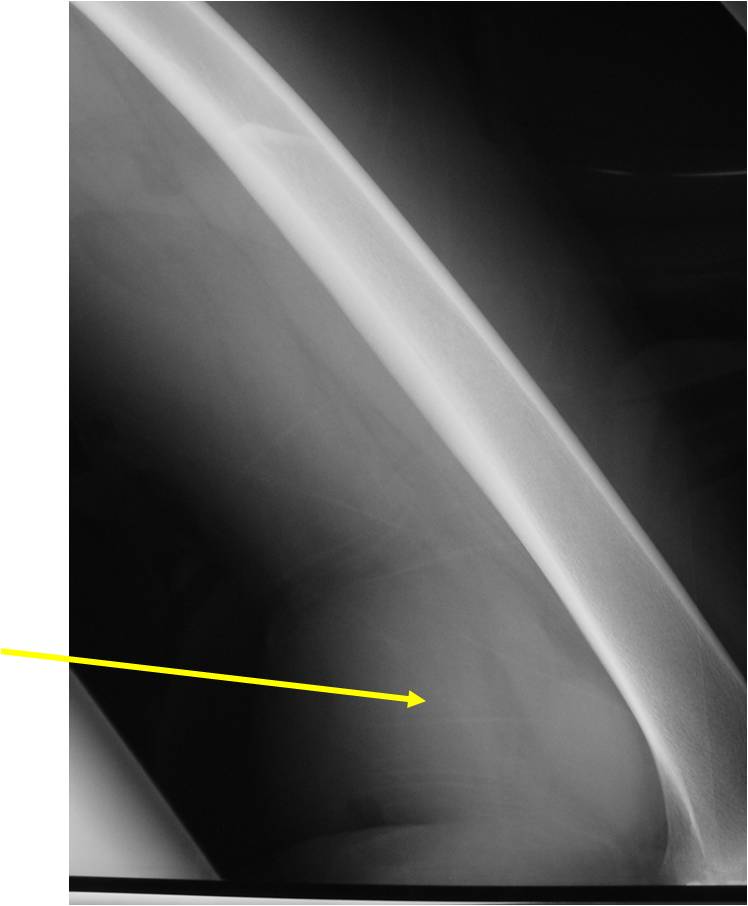

- Aggressive motheaten to permeative lesion

- Indistinct border in most cases

- Osseous destruction with a soft tissue component

- Chondroid matrix calcification may be present (60-70% of cases)

- Soft tissue mass